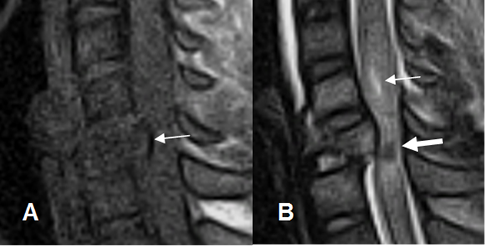

Fig 180 A. Lesión medular mixta.

Fig 180 B. Lesión medular. Igual paciente anterior.

A: RM sagital en T2. Medula engrosada y con zonas hiperintensas, por edema. Hay canal estrecho asociado.

B: RM sagital en T2 y C: RM sagital en T1. Control posterior, donde se aprecia disminución de los cambios inflamatorios. En T1 no hay áreas hiperintensas, con lo que se descarta la contusión hemorrágica.

Fig 181. Sección medular.

A y B: RM sagital en T2. Solución de continuidad en el cordón medular por sección y retracción de los extremos.